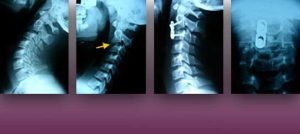

L’Institut Chiari de Barcelona és un centre neuroquirúrgic d’alta especialització dedicat al diagnòstic i tractament de malalties relacionades amb la columna vertebral i el cervell, centrat en el concepte clínic de la malaltia del Filum terminale. Entre les patologies que tracta s’inclouen: